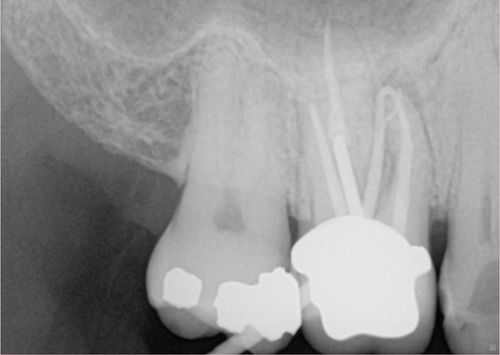

Apicoectomy

Root canal and Apicoectomies